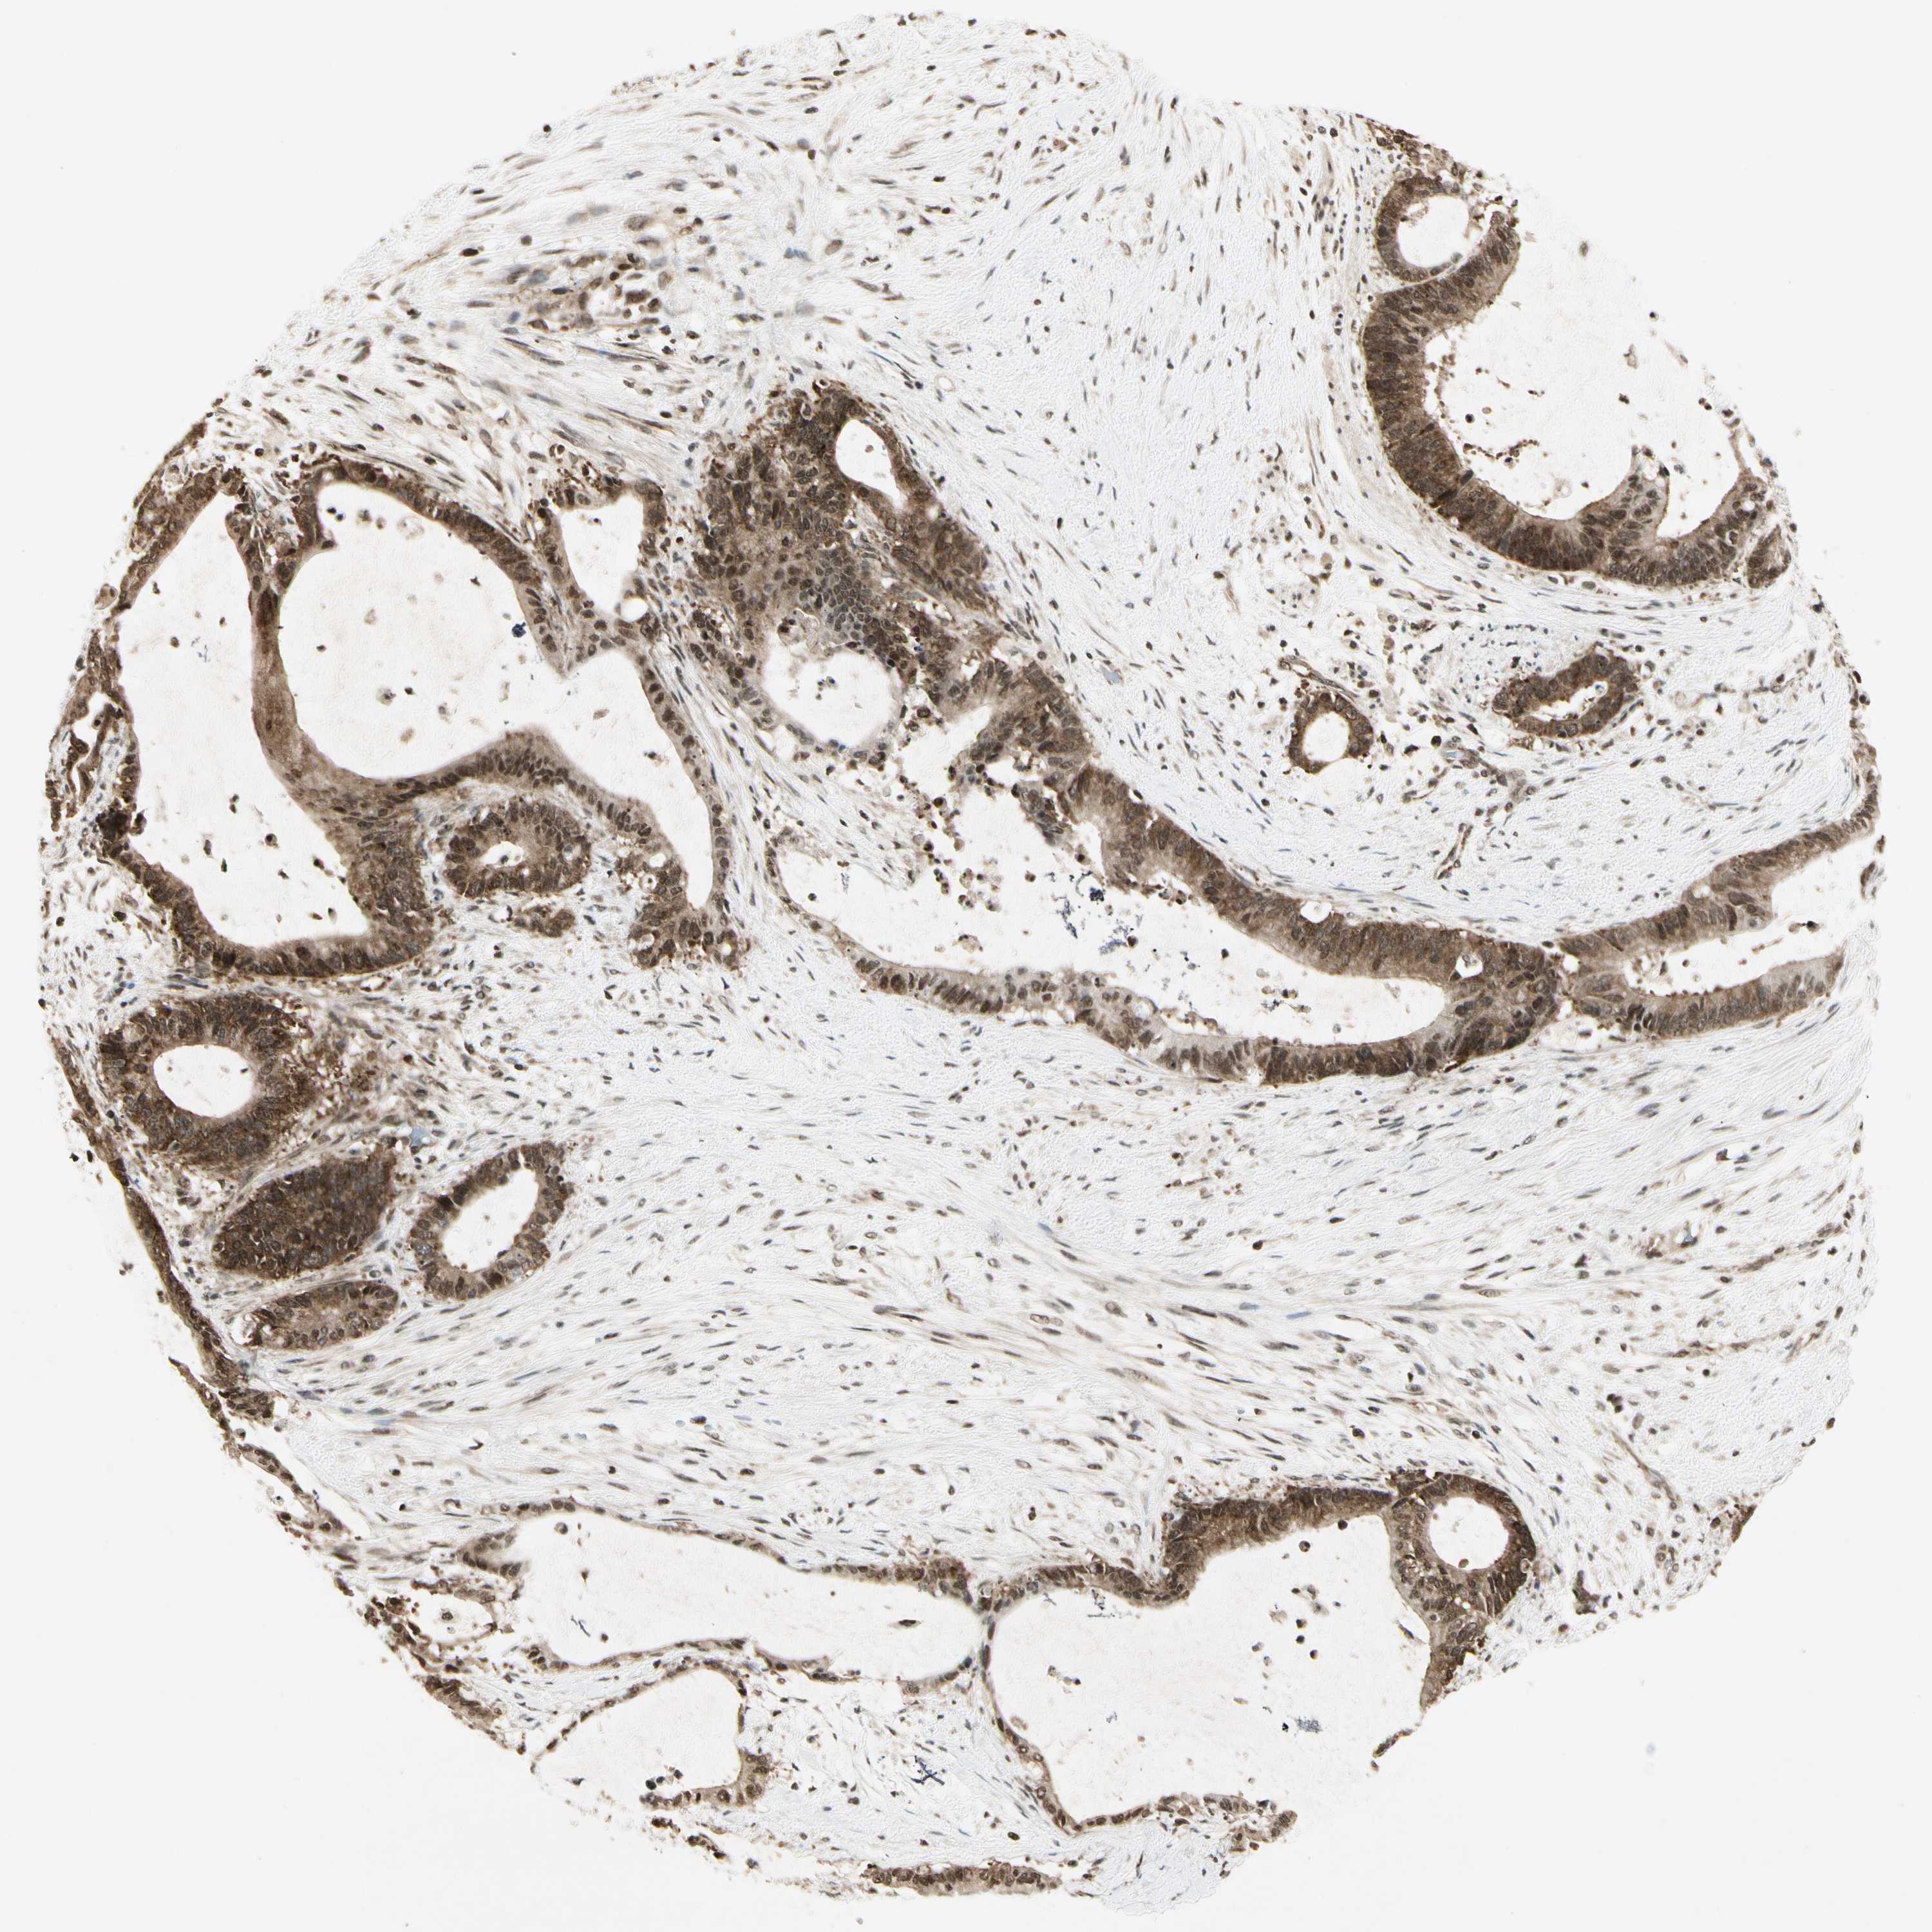

LIVER CANCER - Protein expressioni

A mouse-over function shows sample information and annotation data. Click on an image to view it in a full screen mode. Samples can be filtered based on level of antibody staining by selecting one or several of the following categories: high, medium, low and not detected. The assay and annotation is described here.

Note that samples used for immunohistochemistry by the Human Protein Atlas do not correspond to samples in the TCGA dataset.

Antibody stainingi

Antibody staining in the annotated cell types in the current human tissue is reported as not detected, low, medium, or high, based on conventional immunohistochemistry profiling in selected tissues. This score is based on the combination of the staining intensity and fraction of stained cells.

Each image is clickable and will lead to virtual microscopy that enables deeper exploration of all samples and also displays staining intensity scores, fraction scores and subcellular localization as well as patient and tissue information for each sample.

Antibody HPA045271

Antibody CAB009344

Staining

High

Medium

Low

Not detected

Intensity

Strong

Moderate

Weak

Negative

Quantity

>75%

75%-25%

<25%

None

Location

Nuclear

Cytoplasmic/membranous

Cytoplasmic/membranous,nuclear

Cholangiocarcinoma

Carcinoma, Hepatocellular, NOS